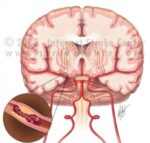

Porážka. Mŕtvica. Mozgový infarkt. Iktus. Toto všetko sú rôzne označenia pre rovnakú diagnózu. Ľudovo sa jej hovorí najčastejšie porážka. Vyplýva to pravdepodobne z najčastejšieho osudu chorých… mŕtvica zmenila človeka natoľko, že už nikdy nebol ako predtým, mal zjavné poruchy pohybu, reči, citlivosti. Nezriedka sa stalo, že pacient po mŕtvici do niekoľkých minút či hodín zomrel. Príčinou mozgovej príhody je náhle či... - Tranzientný ischemický atak – TIA

Veľmi často pred závažnou cievnou mozgovou príhodou príde prechodne tzv. tranzientný ischemický atak – TIA, „predzvesť“ potrenciálne nezvratného stavu. Keďže je táto udalosť prechodná, pacienti jej často neprikladajú dostatočnú pozornosť. Je však potrebné liečiť a diagnostikovať tento prechodný atak rovnako ako cievnu mozgovú príhodu. A veľmi rýchlo. Riziko, že sa TIA zopakuje, alebo sa po TIA udeje mozgová príhoda, je... - Prieskum starostlivosti o pacientov s TIA (tranzitórny ischemický atak)